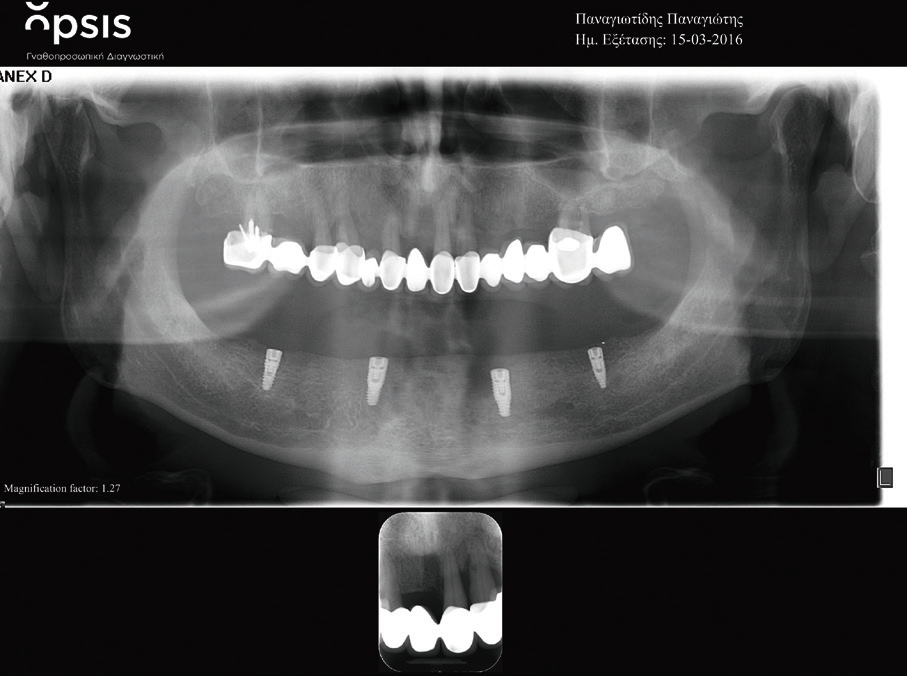

Nach einer weiteren siebenwöchigen Einheilungszeit wurden die Implantate freigelegt und mit Gingivaformern mit Platform Switch Ausführung (PS HP, BEGO Implant Systems) versorgt (Abb. 7).

Zwei Wochen später wurde die Abformung der Implantate durchgeführt. Nach weiteren zwei Wochen erfolgte die definitive prothetische Versorgung des Patienten.